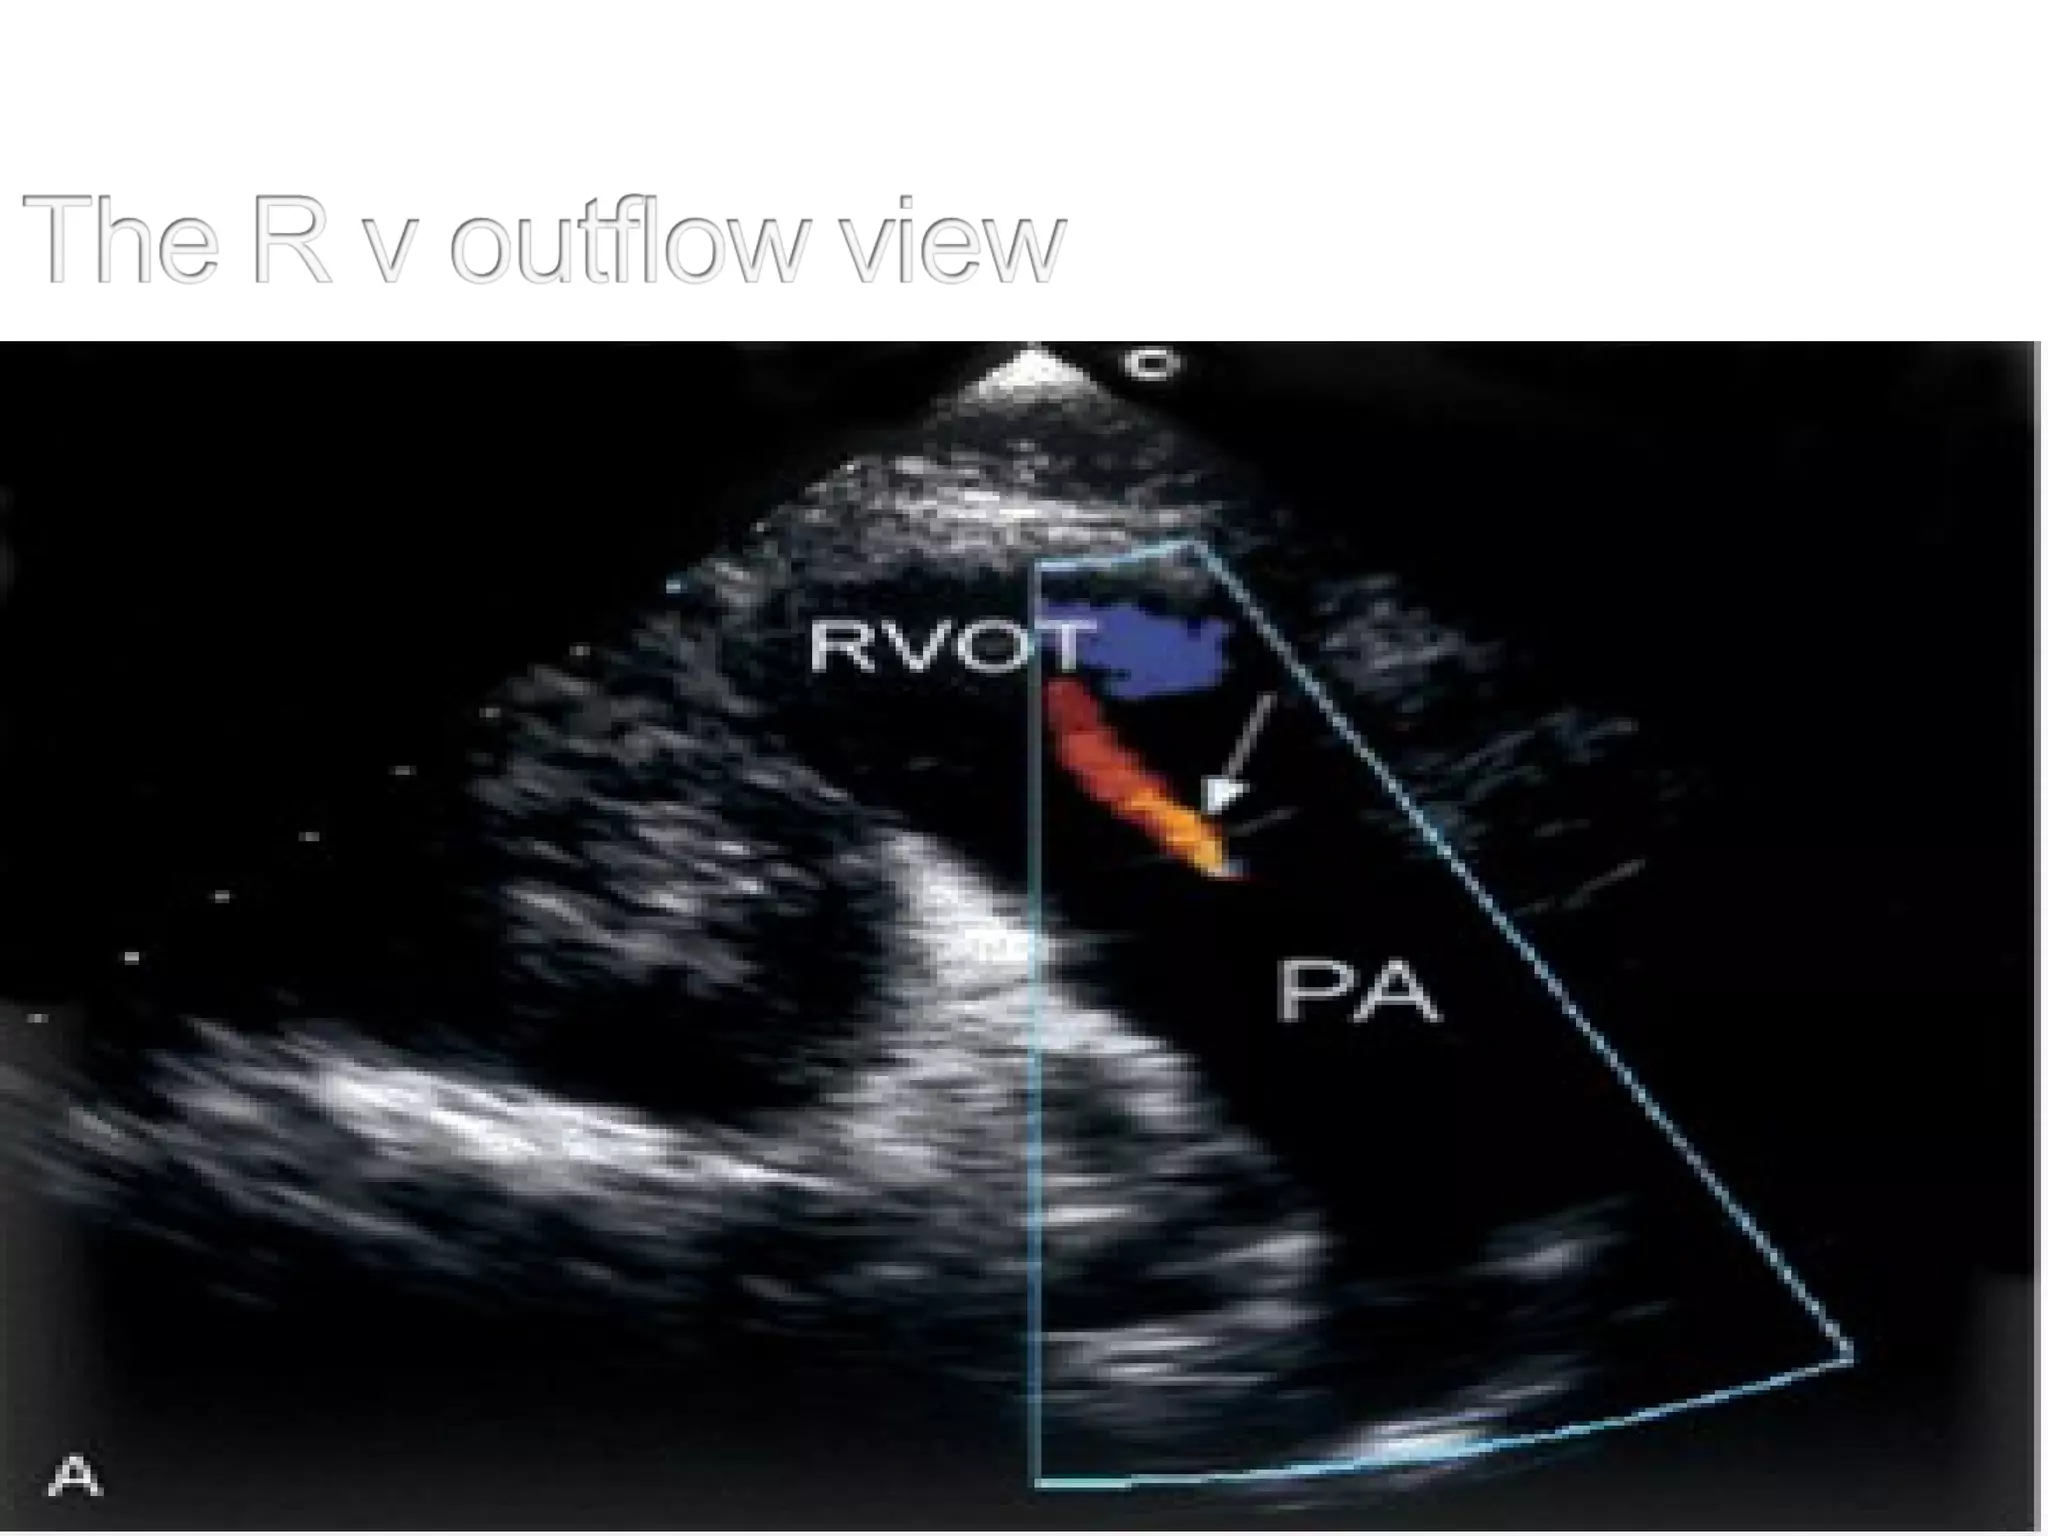

Tilting the planefar anteriorly LVOT not seen Trabeculated &outflow of RV, pulm valve, part of PA